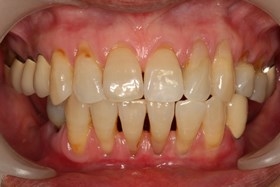

術前缺牙無法咀嚼